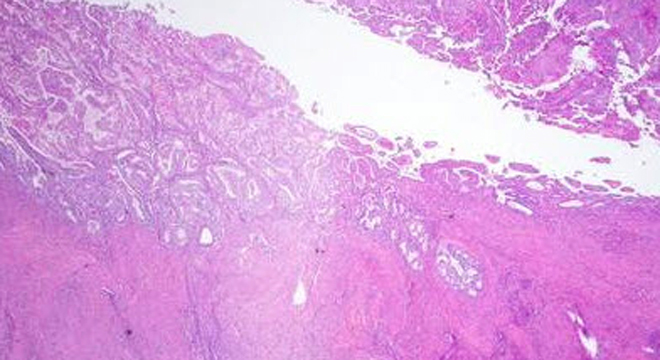

Gebärmutterkrebs: Gebärmutterschleimhaut unter dem Mikroskop